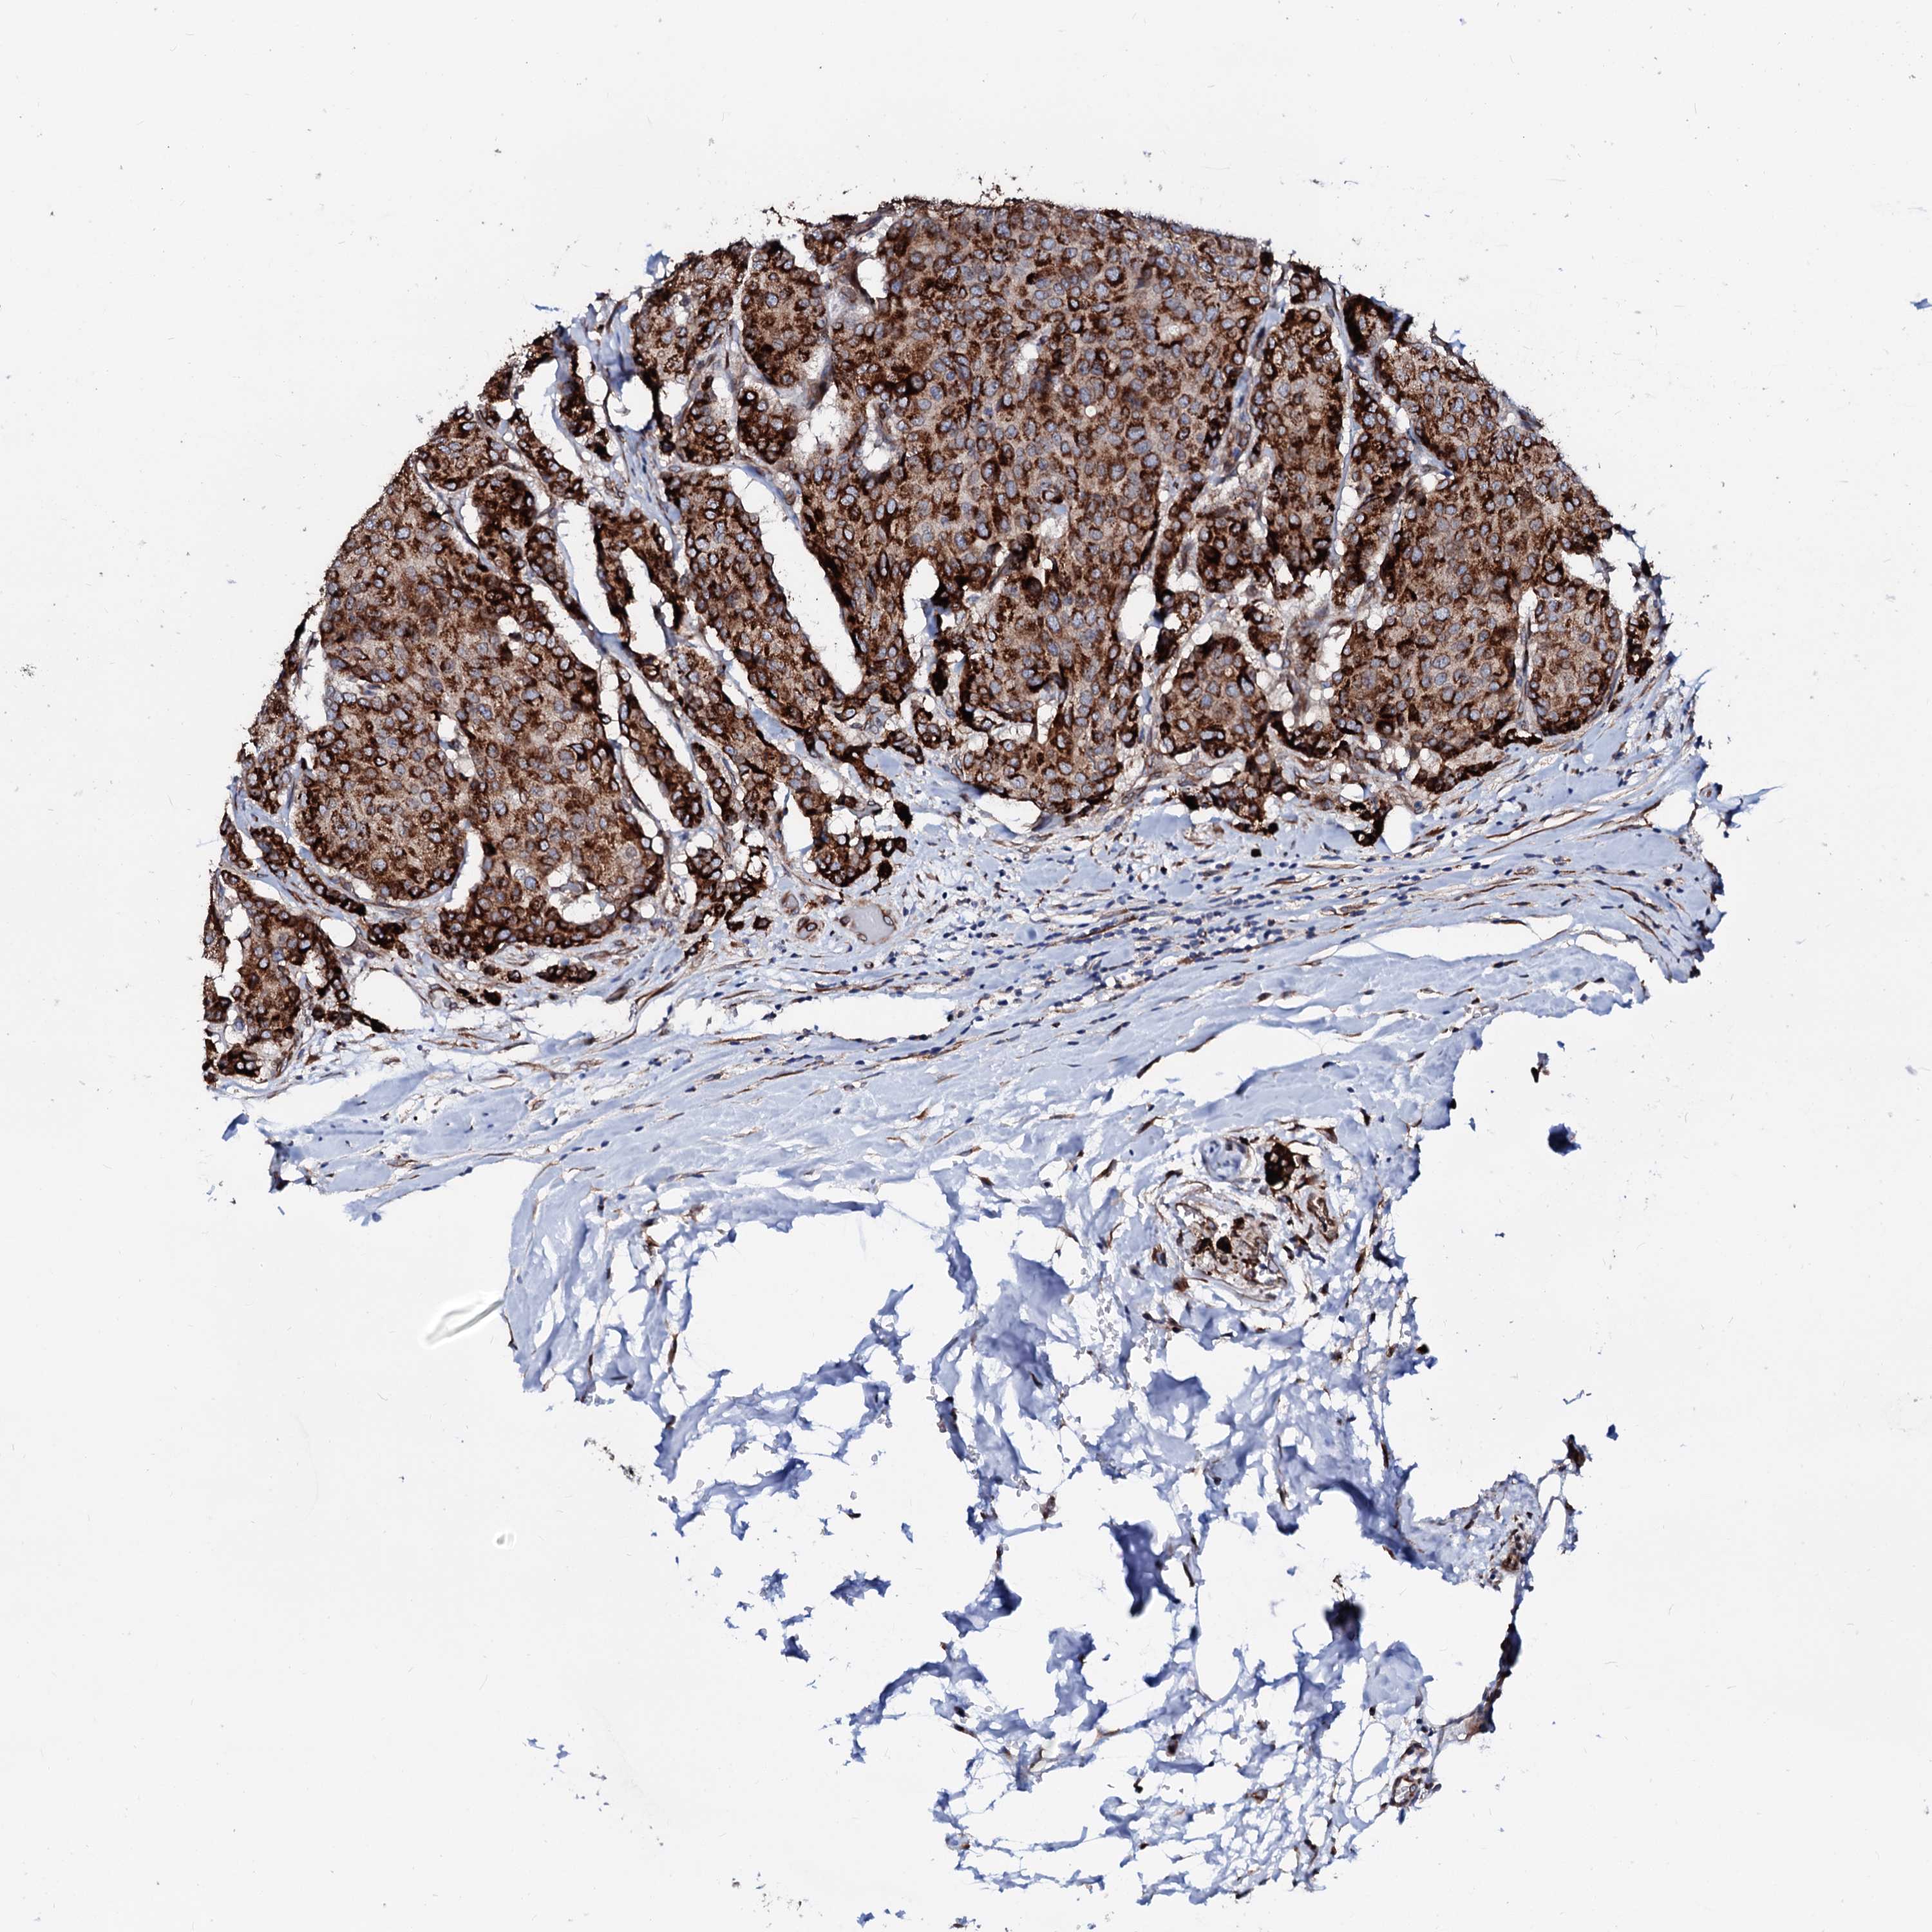

BRCA TCGA BRCA VALIDATION PROTEIN EXPRESSION

ANTIBODIES

AND

VALIDATION